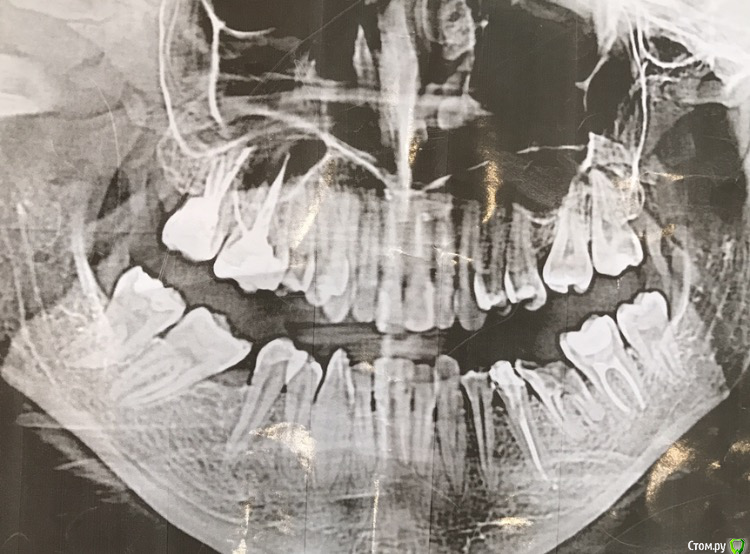

Что имею: три передних депульпированы + штифты стекловолокно.

Внизу два передних аналогичная ситуация.

Вопрос: реально ли с таким прикусом поставить виниры в сочетании с коронками (прессованная керамика)? Интересует зона улыбки ВЧ и НЧ полностью.

Знаю, что лучше было бы брекеты, НО: 70% зубов депульпированы+стоят огромные пломбы (врачи говорят по хорошему коронки надо ставить), плюс трещины. Боюсь, что сниму брекеты вместе с зубами. По итогу опять вернусь к коронкам, соответсвенно очень не хочу тратить время на носку этих конструкций.

П.С. Фото прилагаю, снимок сделан недавно. Потом узнала, что плохой. Но на данный момент это все, что у меня есть. Надеюсь, на нем Вам более--менее понятно состояние полости рта.